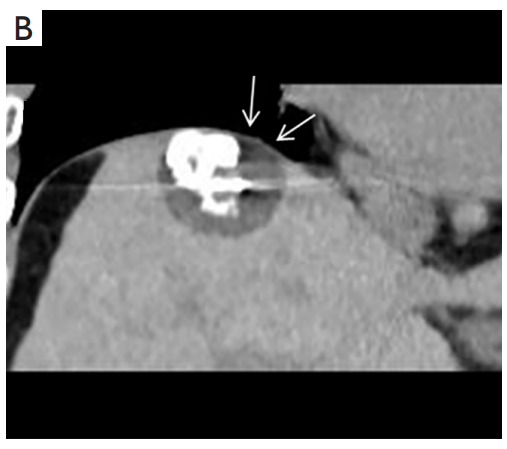

③ 高危部位術(shù)中消融情況:冠狀面CT圖像經(jīng)多平面重建冷凍消融時(shí),腫瘤完全被冰球(箭頭)覆蓋。